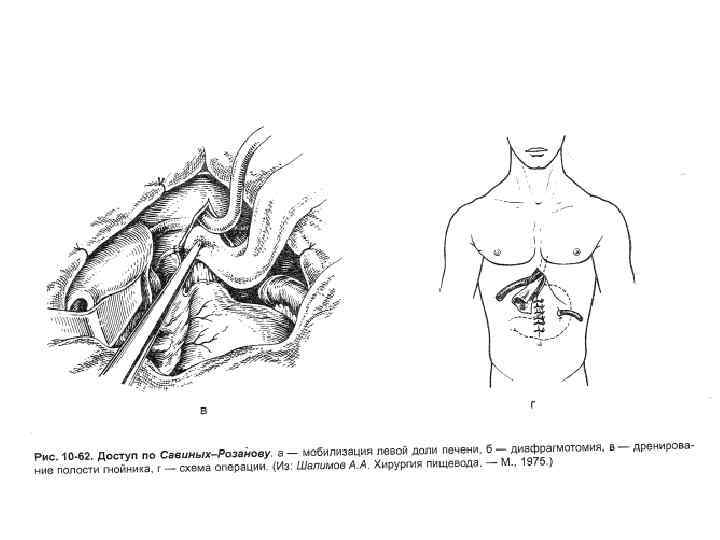

• Техника. Положение больного на спине с подложенными на уровне лопаток валиком. Выполняют верхнесрединную лапаротомию. • После ревизии брюшной полости рассекают печеночно-диафрагмальную, пищеводно-селезеночную, желудочно-пищеводную связки.

• Техника. Положение больного на спине с подложенными на уровне лопаток валиком. Выполняют верхнесрединную лапаротомию. • После ревизии брюшной полости рассекают печеночно-диафрагмальную, пищеводно-селезеночную, желудочно-пищеводную связки.

• Пищевод обходят указательным пальцем и берут на держалку. Выполняют саггитальную диафрагмотомию, пересекая кпереди сухожильную часть диафрагмы на протяжении 6 см.

• Пищевод обходят указательным пальцем и берут на держалку. Выполняют саггитальную диафрагмотомию, пересекая кпереди сухожильную часть диафрагмы на протяжении 6 см.

А – мобилизация левой доли печени Б - диафрагмотомия

А – мобилизация левой доли печени Б - диафрагмотомия

• Перед рассечением диафрагмы следует осторожно отделить её от перикарда, чтобы избежать его повреждения. • После этого натягивают пищевод с помощью держалки. • Накладывают гастростому с введением трубки через отдельный разрез слева.

• Перед рассечением диафрагмы следует осторожно отделить её от перикарда, чтобы избежать его повреждения. • После этого натягивают пищевод с помощью держалки. • Накладывают гастростому с введением трубки через отдельный разрез слева.